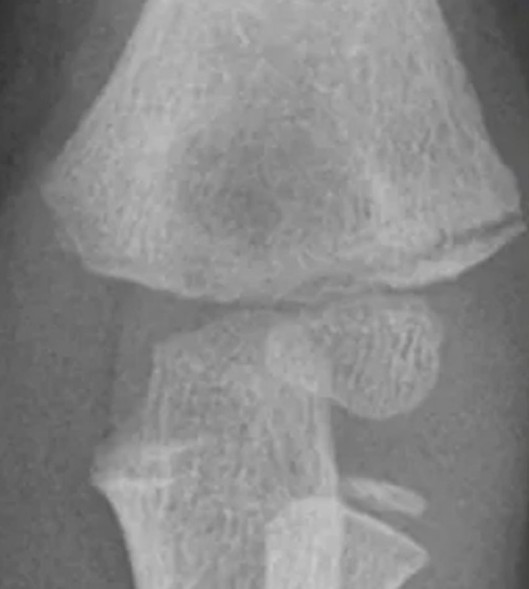

Paediatric lateral condyle fracture

A child is brought in after an unwitnessed fall from monkey bars. She reports left elbow pain with swelling and …

2024 Term 4 Wk 5 Archived

Paediatric elbow injury

A 5-year-old girl presents with a painful elbow following a fall in the playground at school. She is distressed with …

2025 Term 2 Wk 5 Archived